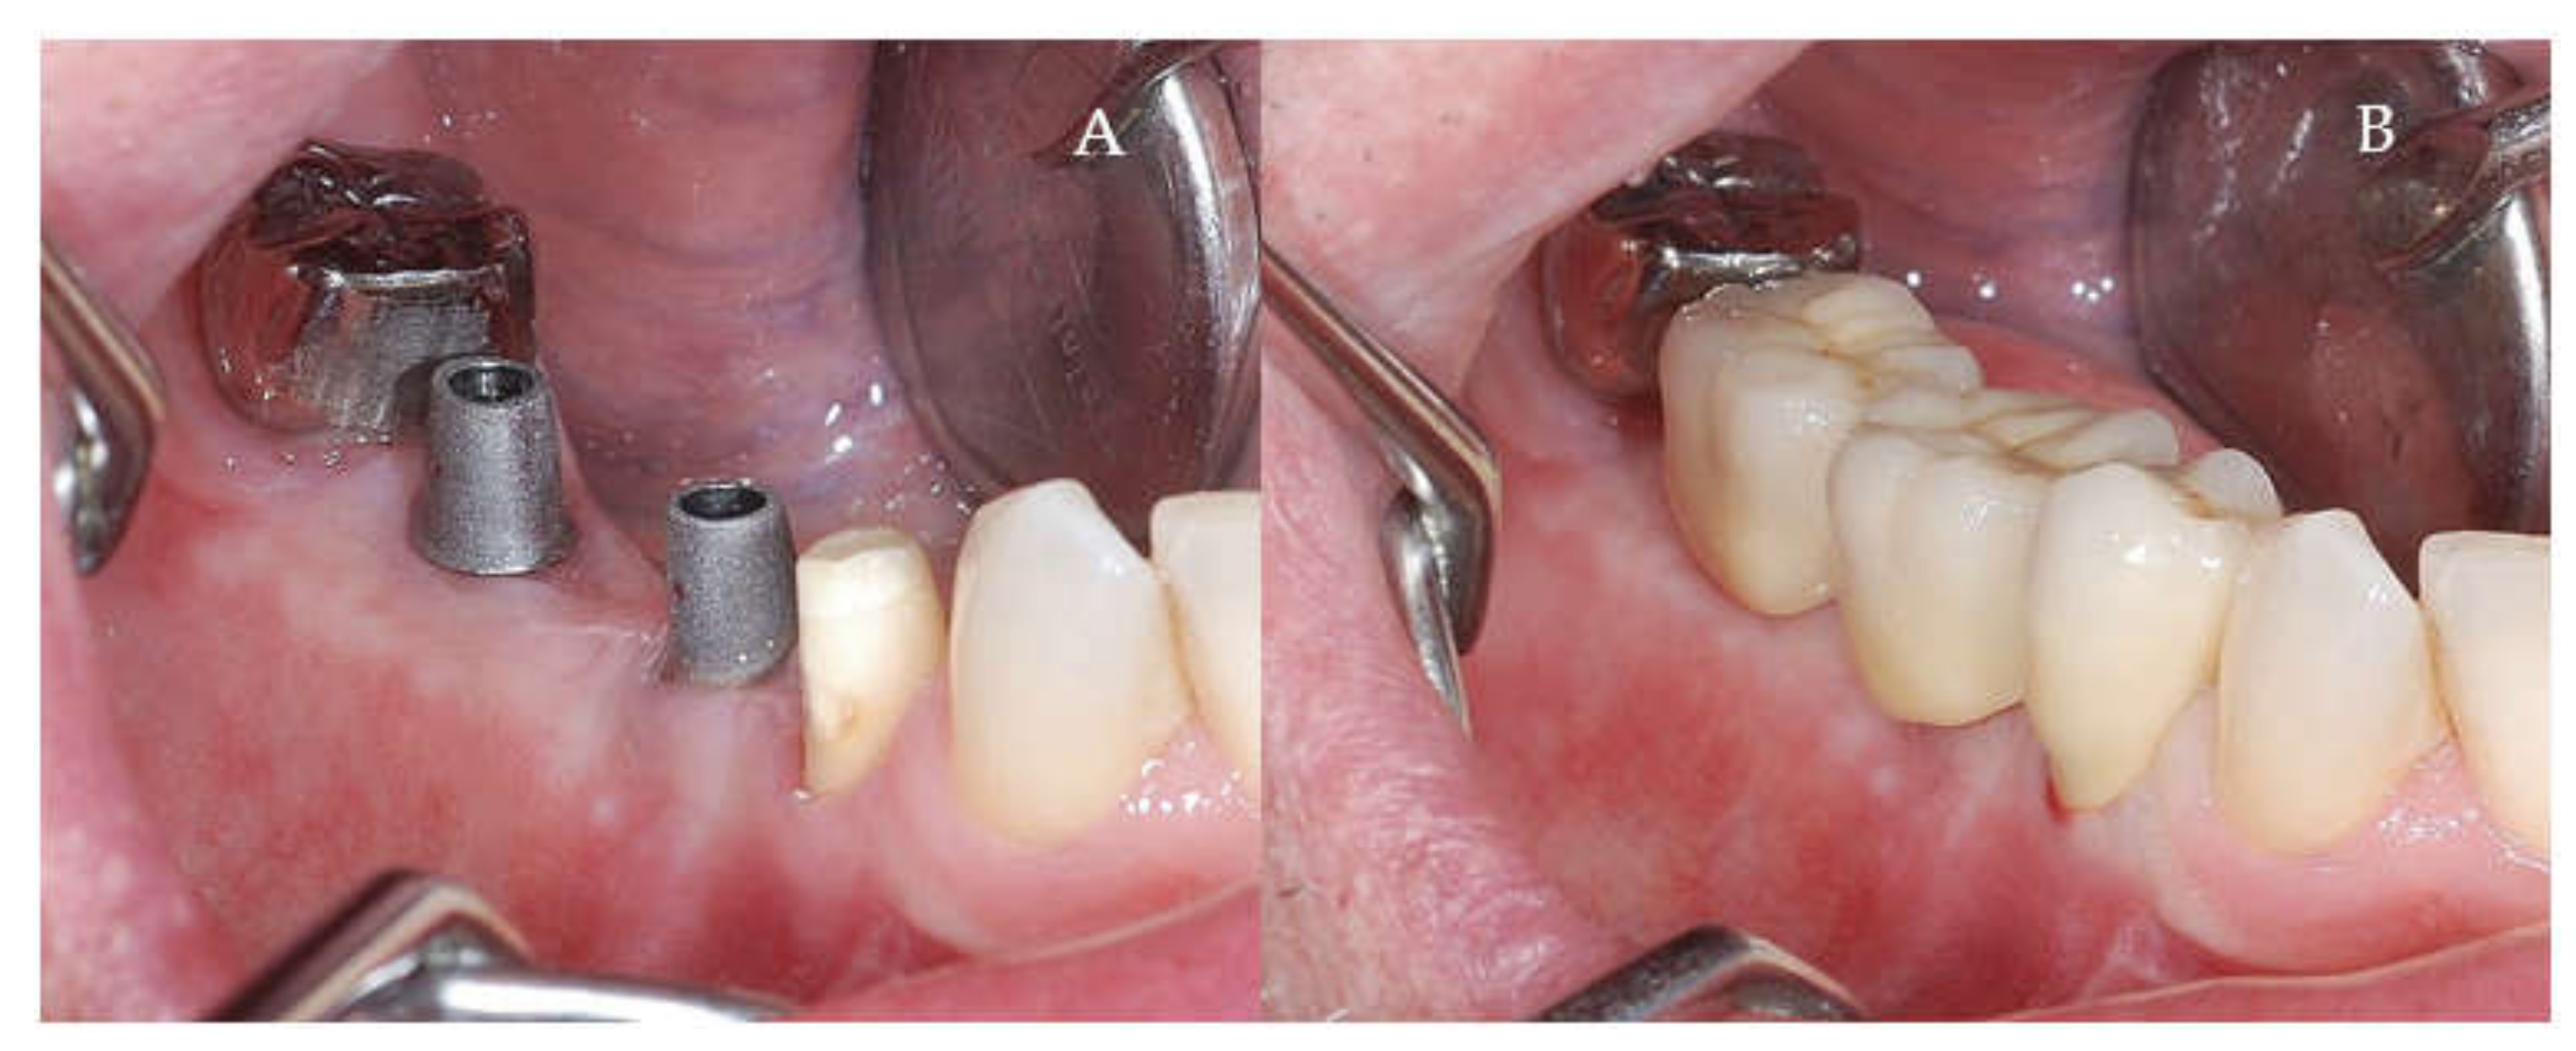

Clinical and CBCT aspects of patient from the test group, describing the stages of S-GBR technique and implant-prosthetic stage, are presented in Figure 1, Figure 2, Figure 3, Figure 4, Figure 5, Figure 6, Figure 7, Figure 8, Figure 9, Figure 10 and Figure 11. CBCT exam allows the evaluation of the horizontal alveolar bone defect and the position of the mandibular alveolar nerf (Figure 1A,B). Figure 1C,D show cross-sectional CBCT aspects of the implant sites. Figure 2 shows the narrowed mandibular alveolar bone with horizontal resorption. Figure 3 shows the exposed buccal surface of the alveolar ridge with severe horizontal resorption, after flap opening. The inserted implants (4.5 mm diameter, 11.5 mm length) and osteosynthesis screws (45° from the occlusal plan) are shown in Figure 4A. The placement of graft (autologous bone and xenograft) and collagen membrane is shown in Figure 4B. Figure 5A shows tension-free sutures, due to periosteal incisions alveolar ridge. Figure 5B shows clinical aspect at 7 months after surgery, with gingival tissue adherent on the reconstructed alveolar ridge. Figure 6 shows OPG aspect at follow-up of 7 months, with osseointegration of the dental implants. Figure 7A shows clinical aspect before osteosynthesis screws removal. Figure 7B shows clinical aspect after osteosynthesis screws removal. Figure 8A shows healthy peri-implant soft tissues. Figure 8B shows repositioning key for perfect position of abutments. Figure 10A,B show clinical aspects of implant-supported prosthetic restoration. Figure 11A,B show CBCT aspects of Osseo integrated dental implants at 24 months follow-up.

Figure 8.

(A,B) Clinical aspects at the second stage surgical session. (A) Aspect before screw removal. (B) Aspect after screw removal.